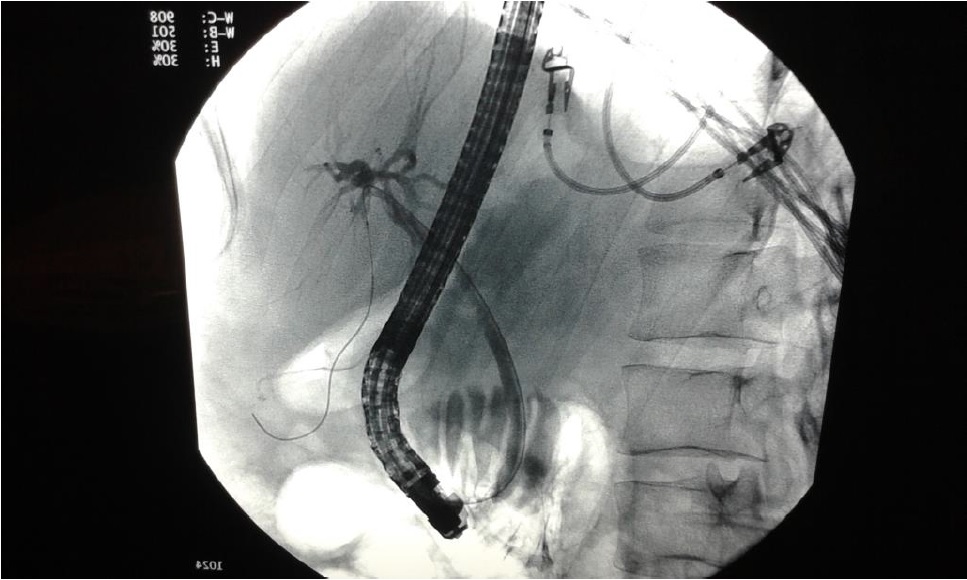

La pancreatitis autoinmune (PAI) es una patología poco frecuente, aunque con una creciente incidencia en países orientales, si bien esto podría deberse a una mayor tasa de detección. Puede asociarse a otras patologías autoinmunes, y se ha descrito su asociación con la enfermedad sistémica por IgG4. La clínica es variada y el tratamiento habitualmente es médico, mediante corticoides.

Se describe un caso clínico diagnosticado.